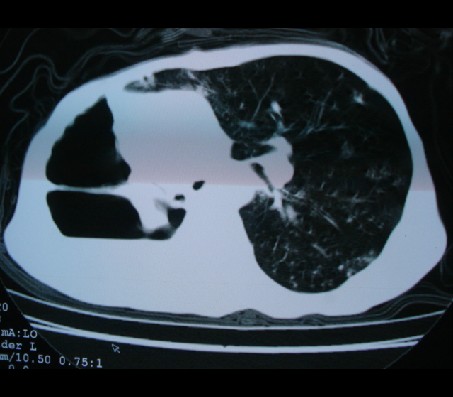

标题: CT17018:肺脓肿?左侧胸腔积液?请会诊! [打印本页]

标题: CT17018:肺脓肿?左侧胸腔积液?请会诊!

男性,65岁,有肺结核病史。

1)两肺继发性肺结核,右肺多发空洞形成并感染,伴左肺支气管播散。2)右侧胸膜增厚、粘连。3)纵隔疝(左→右)。

1)两肺继发性肺结核伴右肺毁损,右肺多发空洞及肺大泡形成并感染,伴左肺支气管播散。右侧液气胸.2)右侧胸膜增厚、粘连。3)纵隔疝(左→右)。